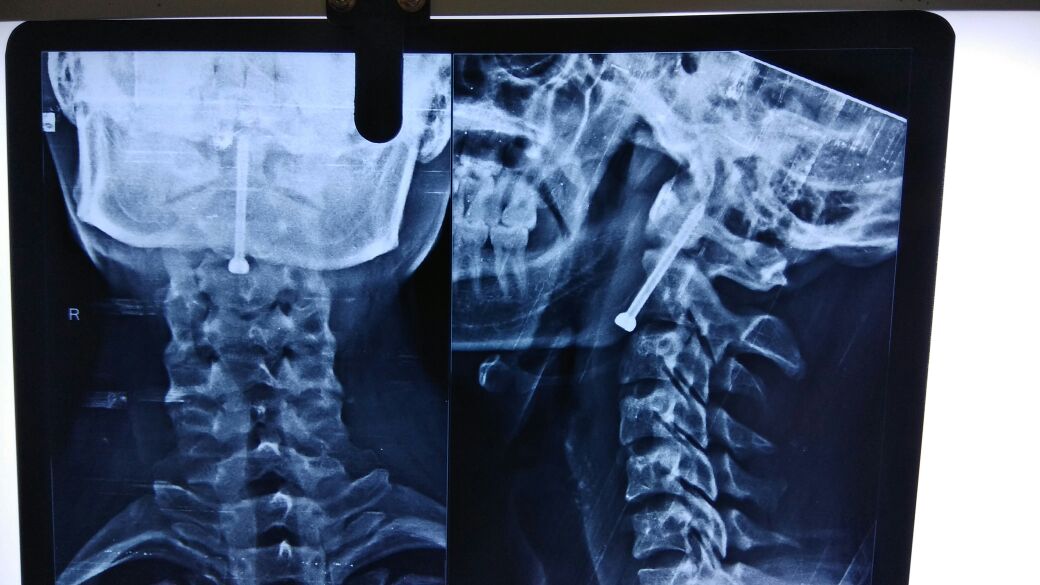

गर्दन की टूटी हड्डी

14 दिन पूर्व मरीज को उसके परिजन पीबीएम के न्यरोसर्जरी विभाग में लेकर पहुंचे। यहां चिकित्सकों ने सभी जरूरी जांचें कराई। सीटी स्केन व एमआरआई कराई गई, जिसमें मरीज की गर्दन की दो नंबर हड्डी में फ्रेक्चर आया। न्यूरोसर्जन डॉ. कपिल पारीक ने बताया कि मरीज के ओडन्टोइड स्क्रू लगाने का निर्णय लिया गया।

इस पर सात दिन पहले मरीज का ऑपरेशन किया। ऑपरेशन चार घंटे चला। मरीज का समय रहते इलाज नहीं किया जाता तो यह हड्डी फिर कभी नहीं जुड़ती। ऑपरेशन खाने व श्वांस की नली तथा खून की बड़ी नसों के बीच से किया गया। स्कू्र डालते समय थोड़ी-सी चूक से मरीज की जान तक जा सकती थी।

रामू की गर्दन की दो नंबर हड्डी में फ्रे क्चर हो गया, जिसे अनडिसप्लेस्ड ओडन्टोइड फ्रेक्चर कहते हैं। ऑपरेशन कर ओडन्टोइड स्क्रू फिक्स किया गया है। अब मरीज को सामान्य होने में करीब छह माह लगेंगे। इस तरह का बीकानेर में पहला ऑपरेशन किया गया है।